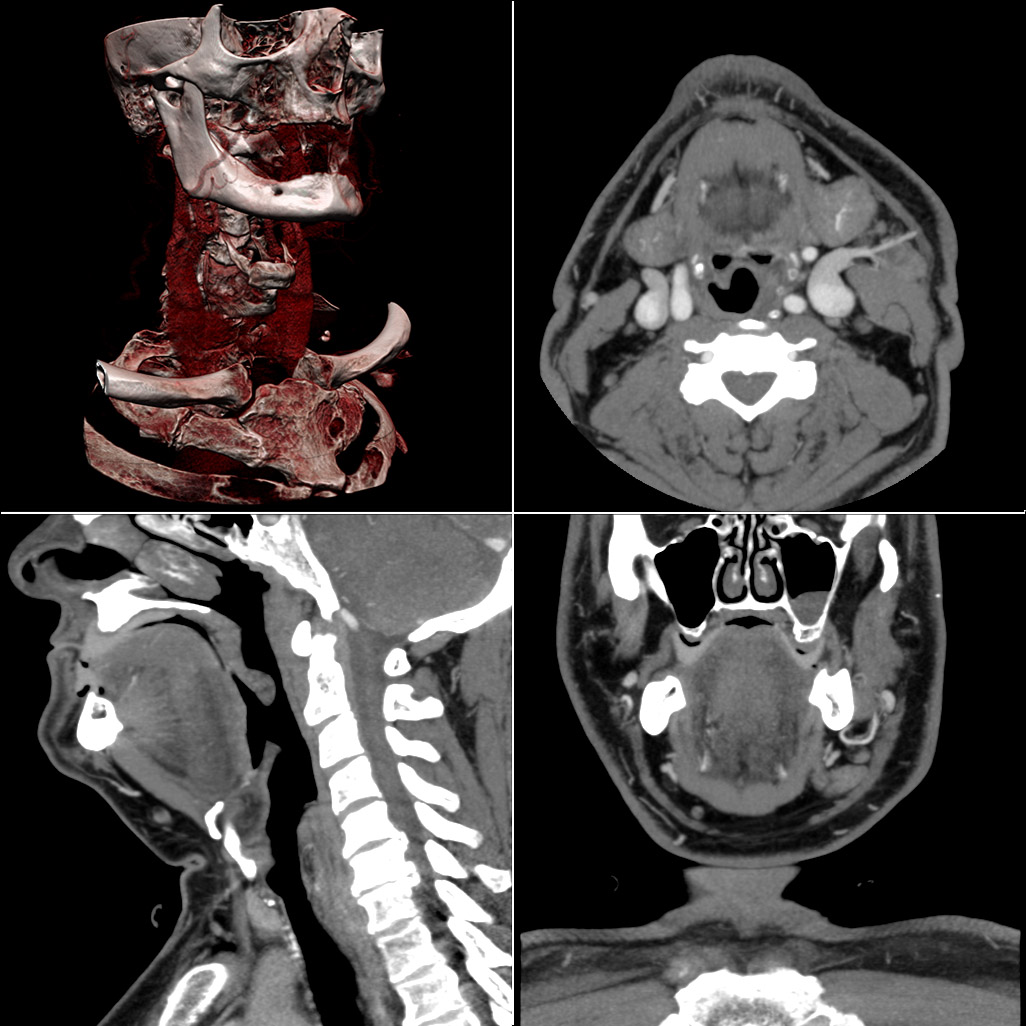

4. 3. 컴퓨터 단층 촬영 (CT)

컴퓨터 단층 촬영(CT) 또는 CT 스캔(이전에는 CAT 스캔으로 알려졌으며, "A"는 "축"을 의미)은 컴퓨터와 함께 X선을 사용하여 연조직과 경조직의 이미지를 생성한다. 이러한 이미지는 환자를 빵처럼 썰어 놓은 것처럼 보인다("토모그래피" – "tomo"는 "slice"를 의미). CT는 진단용 X선보다 더 많은 양의 이온화 X선 방사선을 사용하지만(둘 다 X선 방사선을 사용), 기술 발전으로 CT 방사선량과 스캔 시간이 감소했다.[9] CT 검사는 일반적으로 짧으며, 대부분 숨 참기 시간만큼만 지속된다. 보이는 조직에 따라 방사선 조영제가 자주 사용된다. 방사선사는 이러한 검사를 수행하며, 때로는 영상의학과 의사와 협력하기도 한다(예: 방사선과 전문의가 CT 유도 생검을 수행하는 경우).X선 촬영은 간편성과 경제성이 뛰어나 현재도 건강 검진 등 대부분의 진료 시설에서 사용되고 있다. 자기 공명 영상법(MRI)이 영상의 유용성이 더 높은 경우도 있지만, 응급 상황에서는 헬리컬 스캔, MDCT의 등장으로 CT 촬영 시간이 줄어들어 단순 X선 사진의 비율은 줄어들고 있다. 또한, 방사광 X선을 사용한 CT에서는 매우 세밀한 부분까지 알 수 있어 현미경적인 영상이 기대되고 있다.[32]